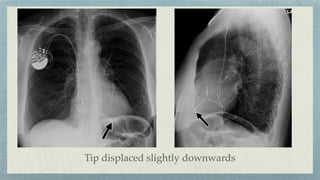

Cardiac Pacemaker

Single lead- RV

Double leads- RV + RA

Triple leads- RV+ RA+ LV

Fracture of the lead

Correct placement

Tip displaced slightly downwards